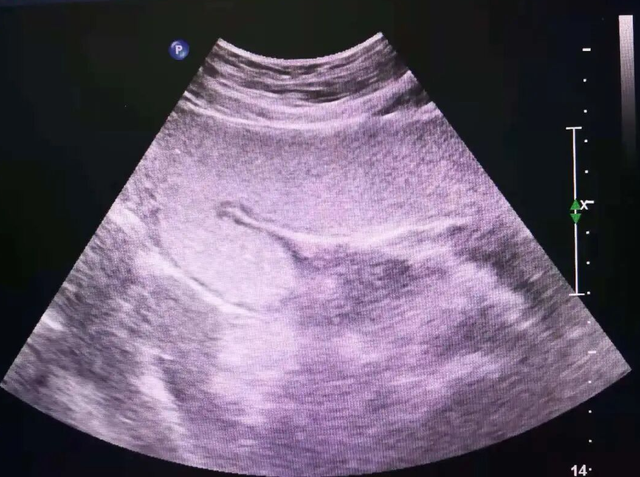

检查时,刘先生喝下一杯特制的像的“米糊”一样的胃肠超声造影剂后,医生通过超声探头实时探查,清晰地看到在他的胃窦部,形成了一个边界清晰的强回声团块,后方伴声影——这正是典型的“胃石”影像!